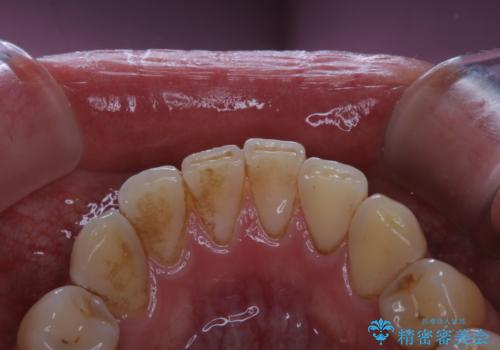

紅茶による着色を1日できれいに

- 紅茶を頻繁に飲むため、歯の黄ばみが気になるとのことでした。PMTC60分コースを行いました。

毎日丁寧に歯磨きをしていても、日常生活での飲食物などにより着色してしまうことはあります。

PMTC(保険外治療)は、毎日の歯磨きで落としきれない汚れや、コーヒ、紅茶・タバコのヤニなどの着色も除去します。目には見えない歯と歯の間・歯肉の境目などに残っているプラーク(歯垢)もしっかり取り除きます。PMTCでは専門的な機械や材料を使用して、徹底的に汚れを除去するため、虫歯・歯周病・口臭予防などにつながります。